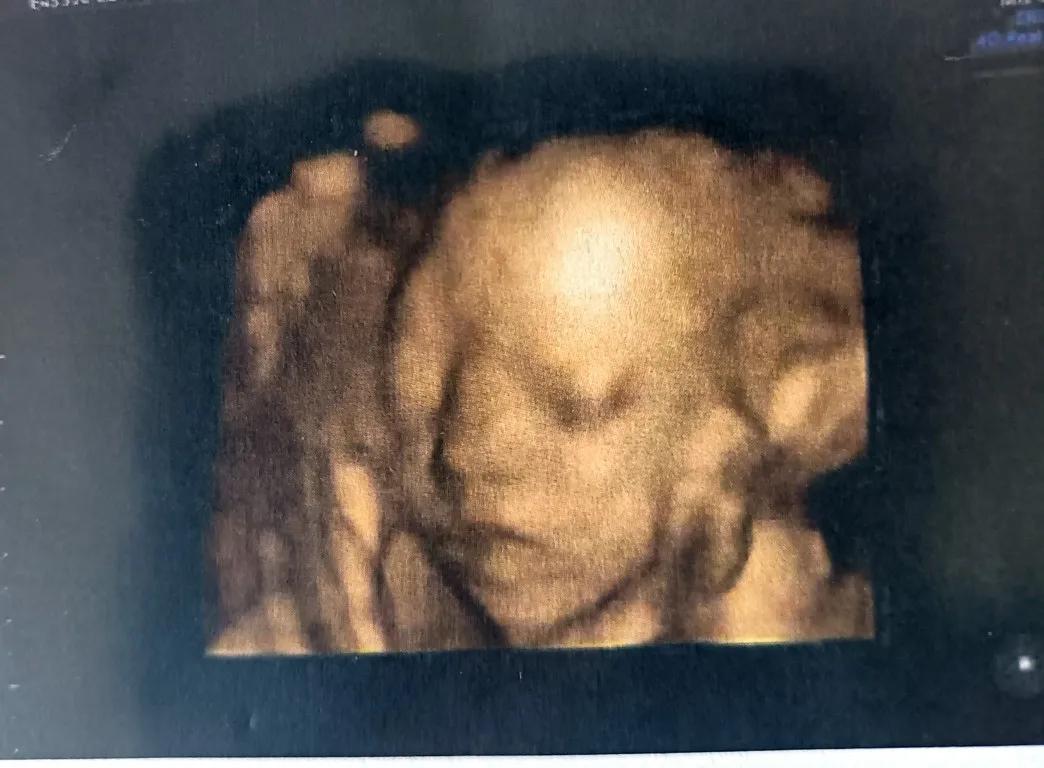

给大家分享一下我姑娘四维的样子